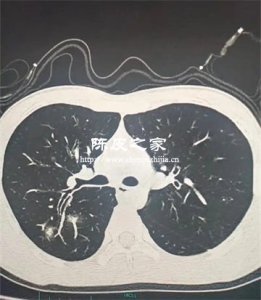

陳皮一般屬于中醫常用藥物,陳皮為臨床最常用的中藥之一,70%以上的中藥處方都加以陳皮調和,提效增益。在中醫學上,陳皮可以用于調理胃腸和肺功能,也可以用于一些肺部炎癥的輔助治療,所以陳皮對肺部是有好處的。

另外,在呼吸系統上,陳皮所含揮發油有刺激性被動祛痰作用,使痰液易咯出,對支氣管有微弱的擴張作用,其醇提物的平喘作用較高。